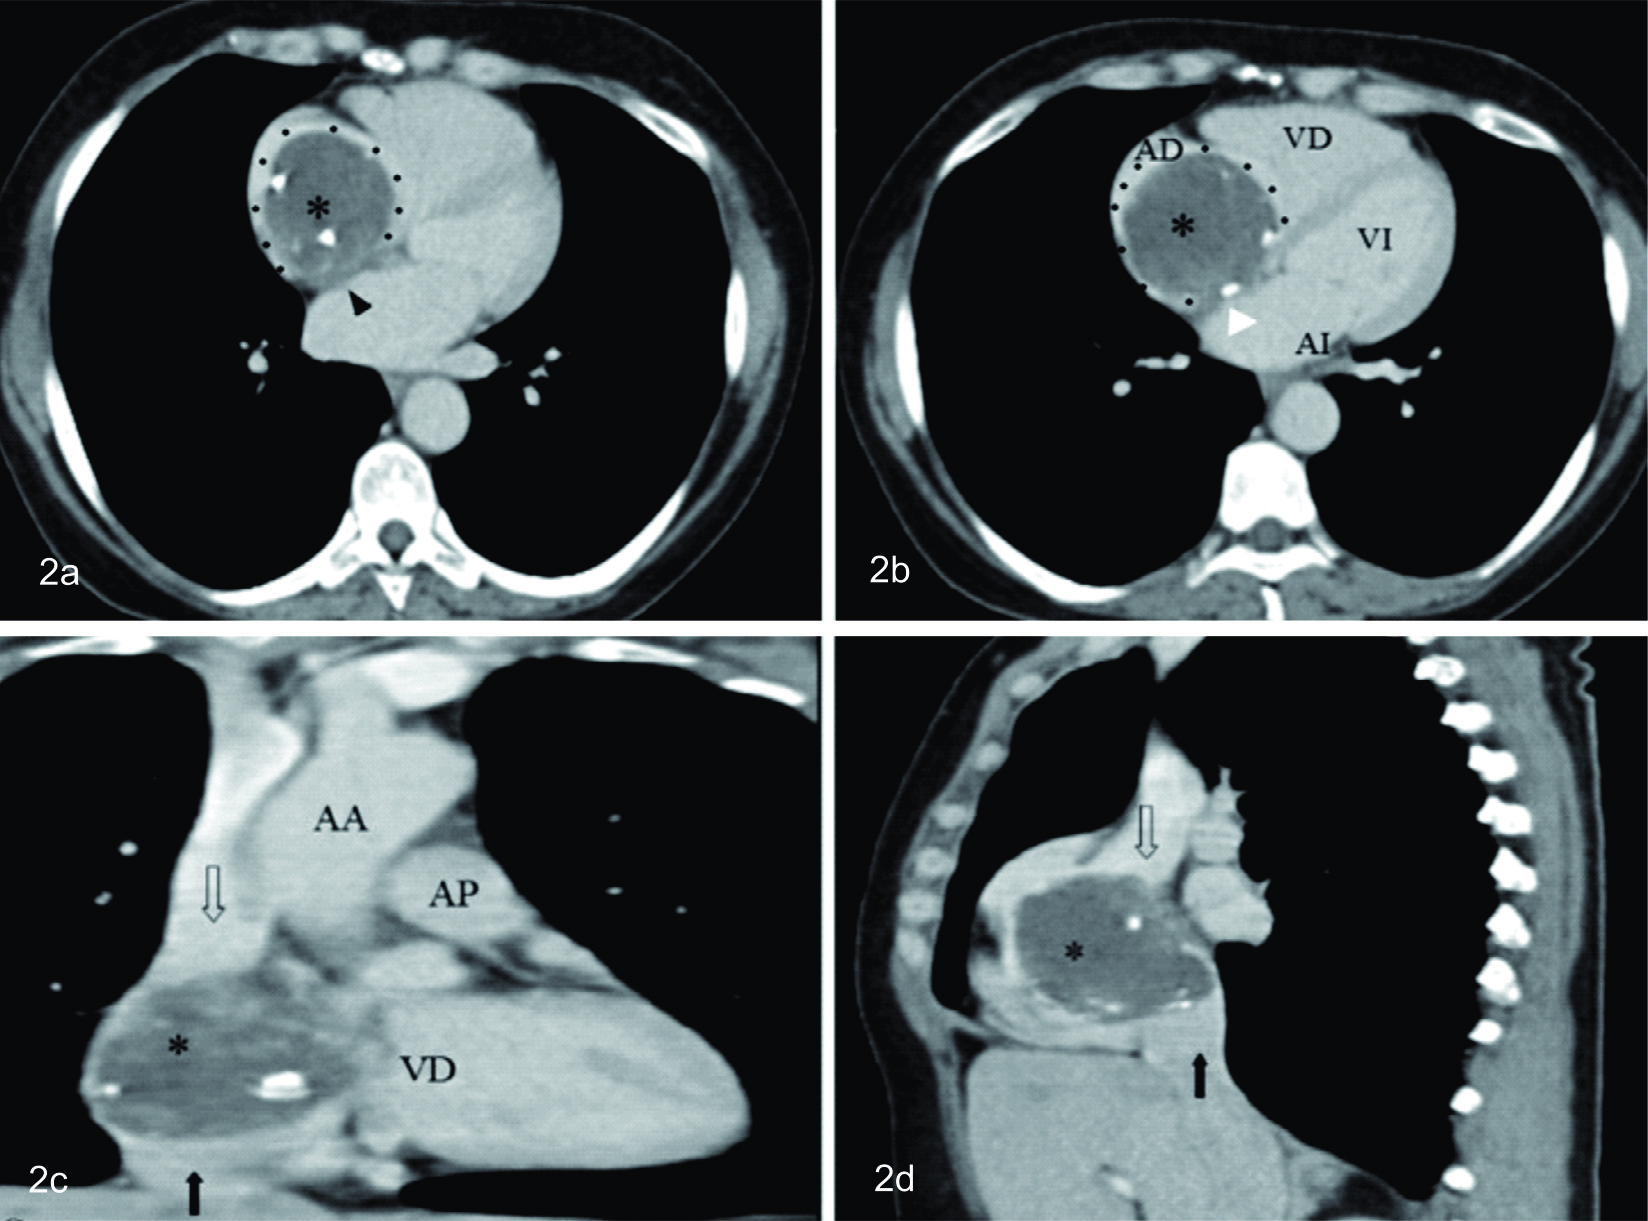

TOMOGRAFÍA COMPUTADA

Cortes tomográficos en el plano axial (a y b), con medio de contraste intravenoso, donde se identifican las cuatro cámaras cardíacas (VD: ventrículo derecho; VI: ventrículo izquierdo; AD: aurícula derecha y AI: aurícula izquierda.

El mixoma (*) aparece como una lesión sólida, esférica, de límites netos, con baja densidad, discretamente heterogénea, con áreas dispersas en su interior de mayor densidad, que pueden estar vinculadas a hemorragia.

Se puede observar el amplio contacto de la masa al septo interauricular (punta de flecha negra) y la presencia de calcificaciones centrales y periféricas, una de las cuales se encuentra a nivel del mencionado septo (punta de flecha blanca). Su gran tamaño expande la aurícula derecha, determinando el pasaje filiforme del medio de contraste en su periferia, el cual la rodea por completo, excepto en su vinculación al septo (puntos negros).

En las reconstrucciones en los planos coronal y sagital (C y d respectivamente) se visualiza el mixoma limitado a la aurícula derecha, sin extensión a las venas cava superior ni inferior.